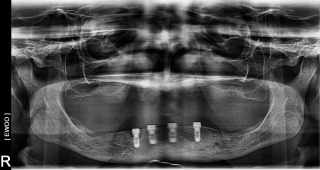

Gloria D.

This patient had been unhappy with her loose lower denture.  Placed four Implants to secure lower denture and she is now happy to report back that she can eat steak!